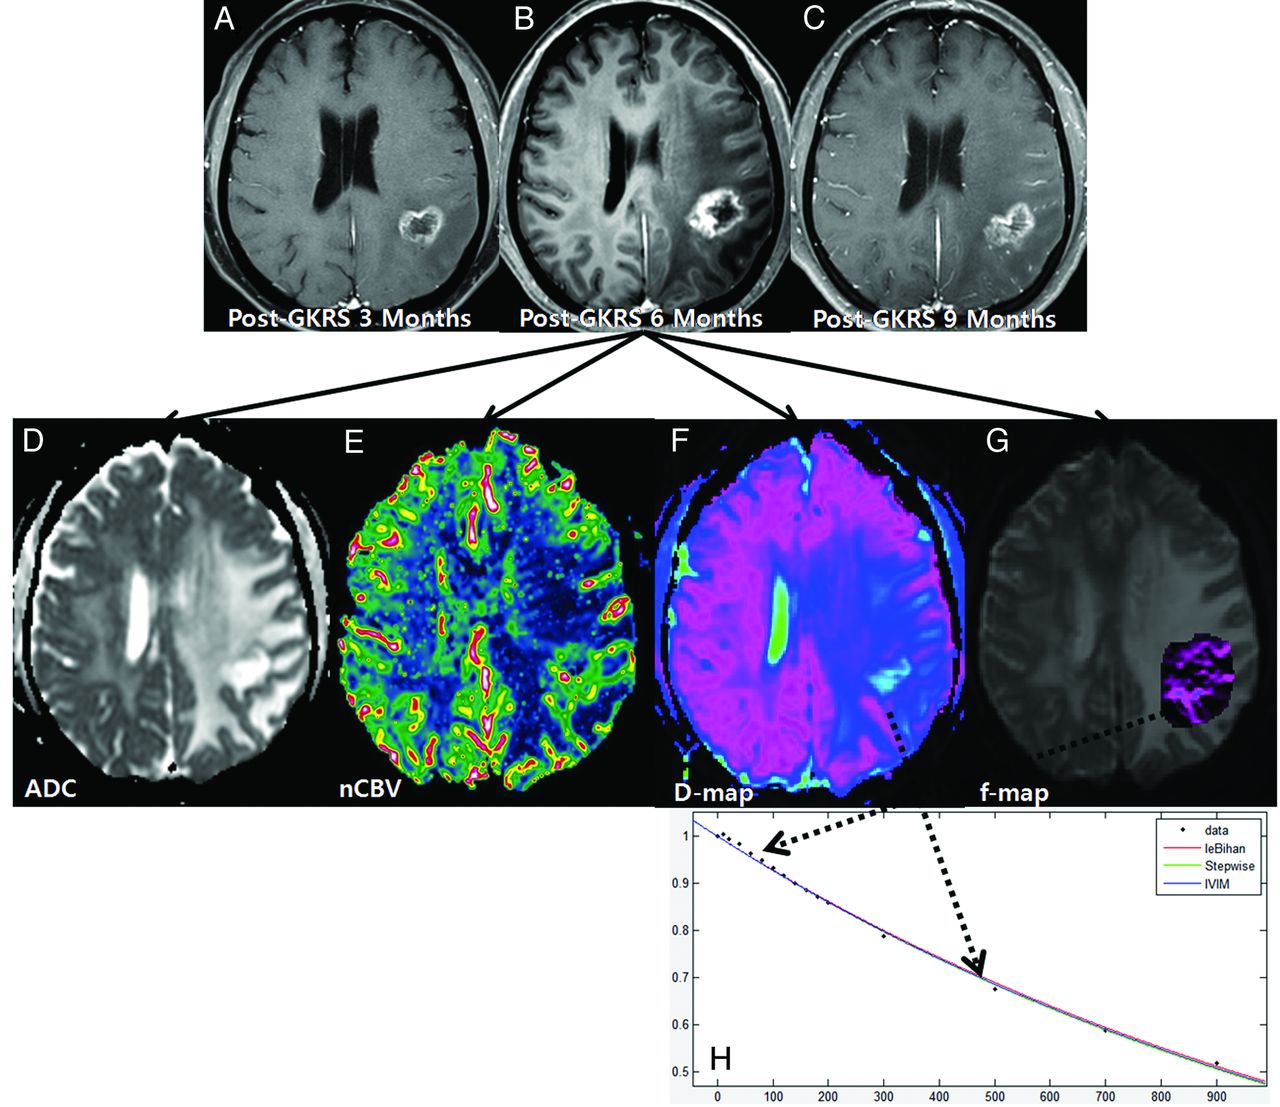

A 61-year-old woman with treatment effect following GKRS. Axial contrast-enhanced T1-weighted images, obtained 3 (A) and 6 months (B) after GKRS, show a progressively enlarging necrotic contrast-enhancing lesion in the left parietal lobe. C, The necrotic contrast-enhancing lesion is stabilized on a subsequent follow-up image obtained 9 months after GKRS, thus indicating treatment effect. The ADC (D) and nCBV (E) maps show no visual decrease of the ADC and no visual increase of the nCBV in the corresponding area of the contrast-enhancing lesion in B, respectively. The D (F) and f (G) maps show no visual decrease of the D value and no visual increase of the f value in the corresponding area of the contrast-enhancing lesion in B, respectively. H, The signal decay curve, plotted as a function of the diffusion b-values, is monoexponential.

Among the 91 study patients, analysis of all of the patients with recurrent tumor and 9 patients with treatment effect showed that the signal decay curve, plotted as a function of the diffusion b-values, was biexponential and ranged from 0 to 900 s/mm2. The recurrent tumor group showed more rapid signal decay than the treatment effect group in the range of lower b-values (b < 200 s/mm2) (Fig 3). In the remaining 43 patients with treatment effect, the signal decay curve was similar to the monoexponential pattern (Fig 2). The f, nCBV, D, and ADC maps of representative cases of recurrent tumor and treatment effect are shown in Figs 2 and 3.

A 54-year-old man with recurrent tumor following GKRS. Axial contrast-enhanced T1-weighted images, obtained 3 (A), 6 (B), and 9 months (C) after GKRS, show a progressively enlarging necrotic contrast-enhancing lesion in the right parietal lobe. The ADC (D) and nCBV (E) maps show a visual decrease of the ADC and a visual increase of the nCBV in the corresponding area of the contrast-enhancing lesion in B, respectively. The D (F) and f (G) maps show a visual decrease of the D value and a visual increase of the f value in the corresponding area of the contrast-enhancing lesion in B, respectively. H, The signal-decay curve, plotted as a function of the diffusion b-values, is biexponential.